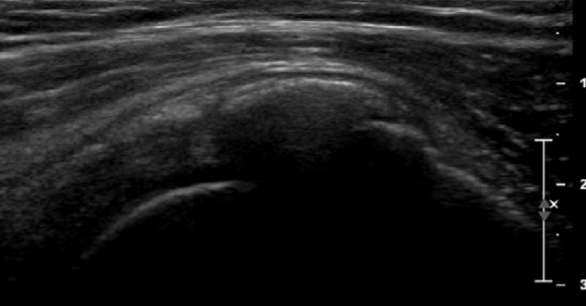

Poleg kliničnega pregleda je potrebna RTG diagnostika in UZ preiskava ramena, v določenih primerih tudi preiskava z magnetno resonanco. Običajno se vnetje zdravi s počitkom, analgetično terapijo, fizikalno terapijo. V določenih primerih svetujemo tudi terapijo z udarnimi valovi (ESWT).

V kolikor so kalcinati večji od 8mm in so enakomerne strukture lahko pod ultrazvočno kontrolo opravimo tudi punkcijo kalcinata in kalcinat izperemo. Poseg se opravi v lokalni anesteziji in traja približno 30 minut. Bolečina lahko traja tudi nekaj dni po posegu. V teh primerih svetujemo jemanje analgetikov. Nekaj dni po posegu priporočamo postopno stopnjevanje aktivnosti, izvajanje vaj, plavanja, nordijske hoje in fizikalne terapije in po 2 -3 mesecih vrnitev željenim aktivnostim.